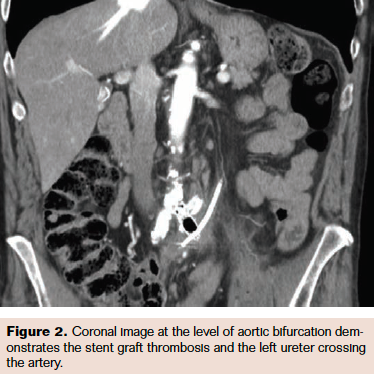

Two years later, the patient underwent computed tomography (CT) to evaluate his ischemic left leg and to facilitate definitive operative planning. CT results revealed thrombosis of his common iliac stent, with an air bubble inside, and a perivascular hematoma involving the left common iliac artery and left ureter.